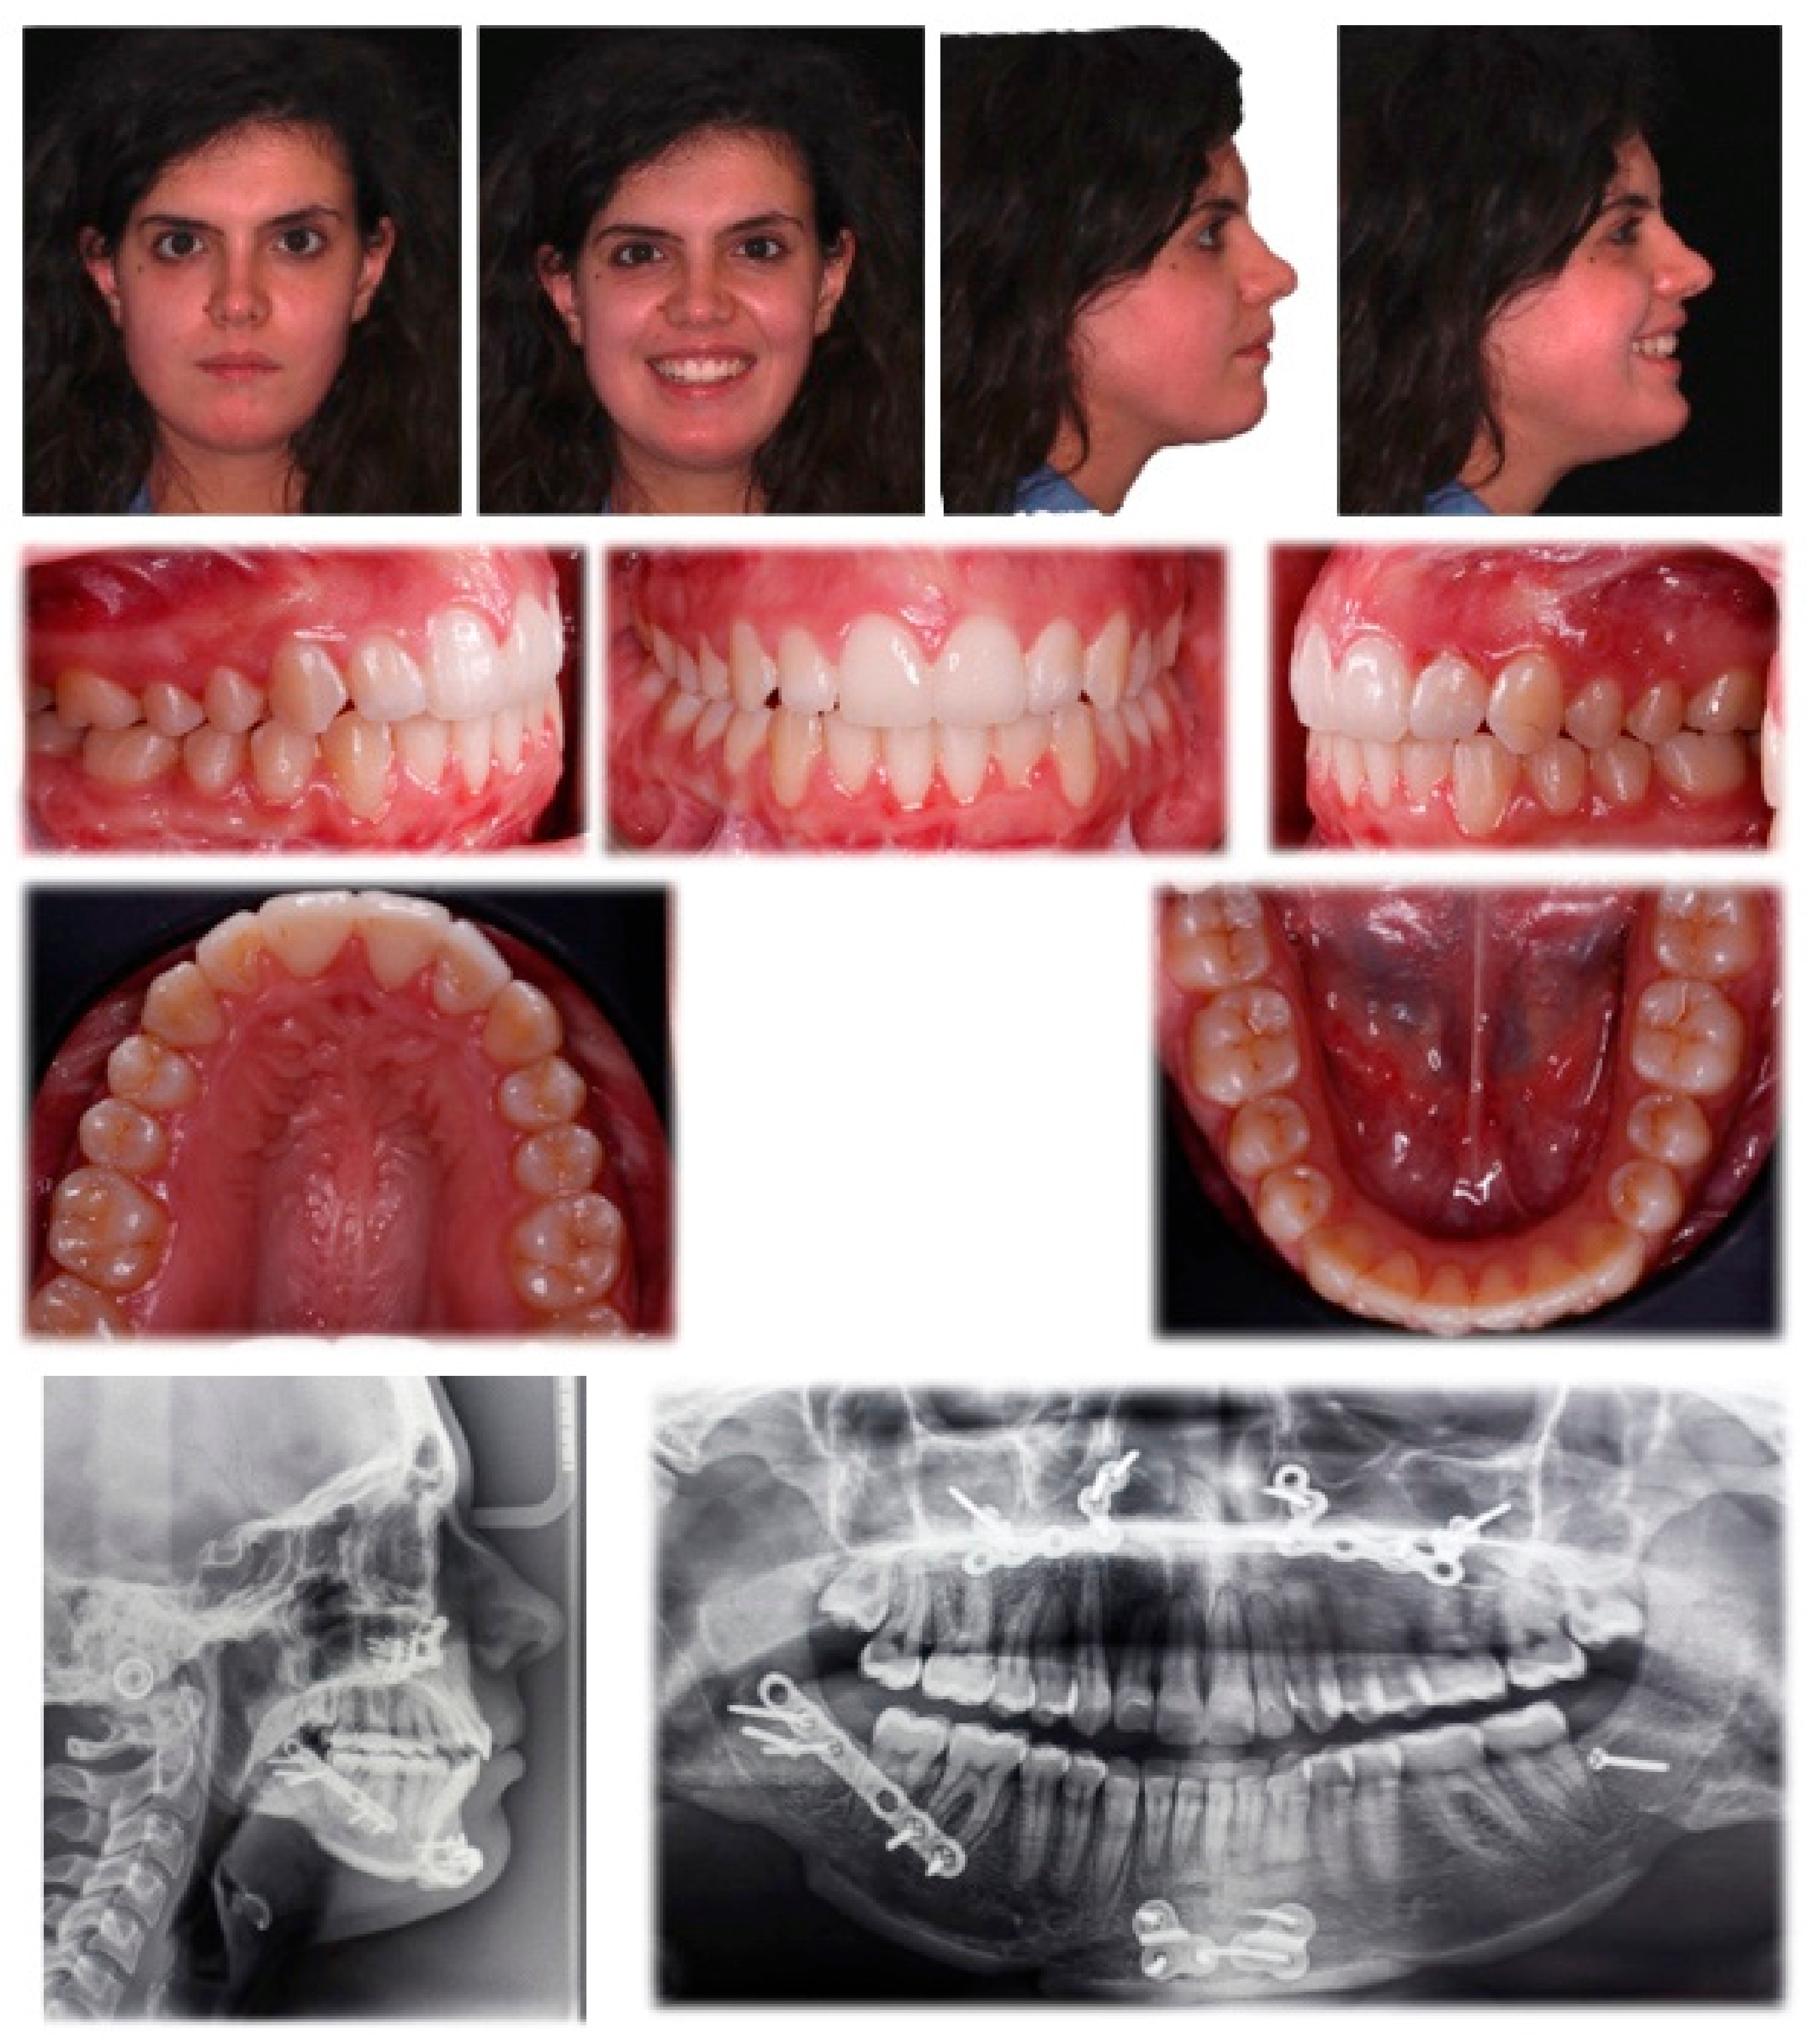

Total treatment time was 15 months, which was slightly increased by the subsequent finishing phase using the aligners and the periodontal aesthetic optimisation. Post-treatment records showed good dental alignment, with proper seating and functional occlusion (Figure 6). The gummy smile and upper canting were normalised, and the soft-tissue profile improved, as was lip incompetence and function. A final panoramic x-ray indicated root parallelism, without significant root shortening or development of other pathologies. No TMD signs or symptoms were found between surgery and the end of the orthodontic treatment [14]. The patient reported a high degree of satisfaction with the aesthetic during treatment and the final results.

Figure 6.

Post Treatment Records. Patient after 15 months of treatment.